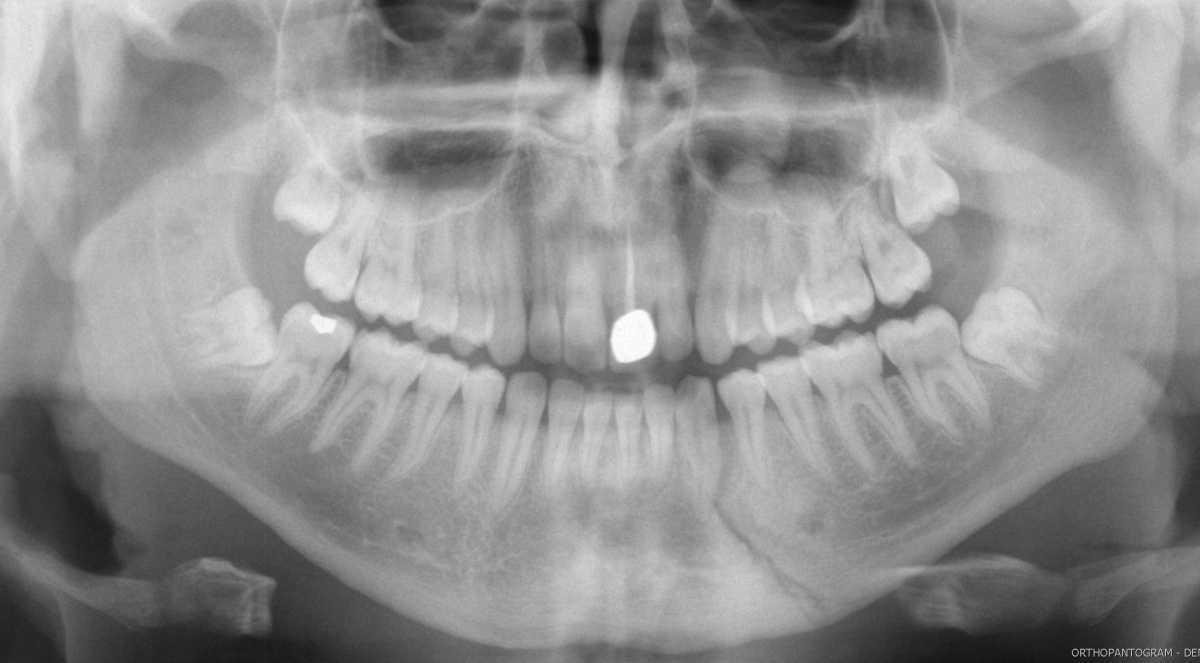

Radiographie panoramique dentaire puis hospitalisation dans le service de chirurgie maxillo-faciale pour une prise en charge au bloc opératoire.

Mise en place d’une antibiothérapie type Augmentin pour les fractures de la portion dentée.

Si fracture sous-condylienne avec trouble de l’articulé dentaire, demander un scanner.